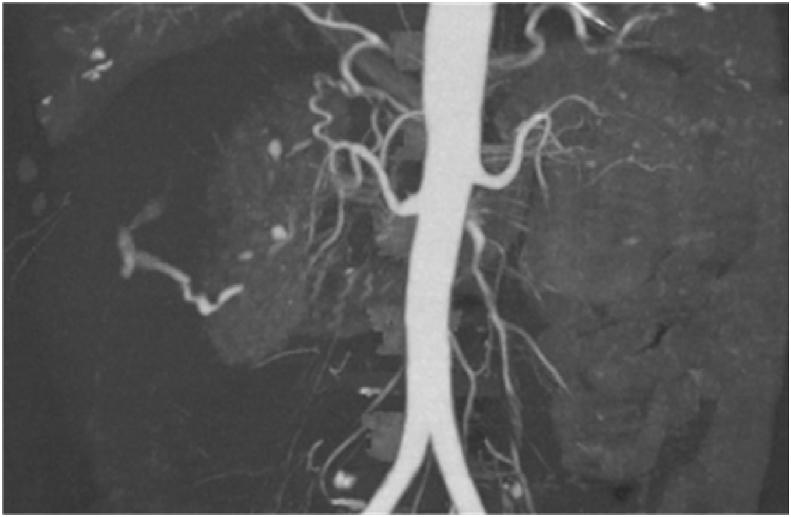

Spontaneous perinephric hematoma in a patient with Granulomatosis with polyangiitis.

Urol Case Rep. 2017 Nov 21;17:26-28. doi: 10.1016/j.eucr.2017.11.003. eCollection 2018 Mar.